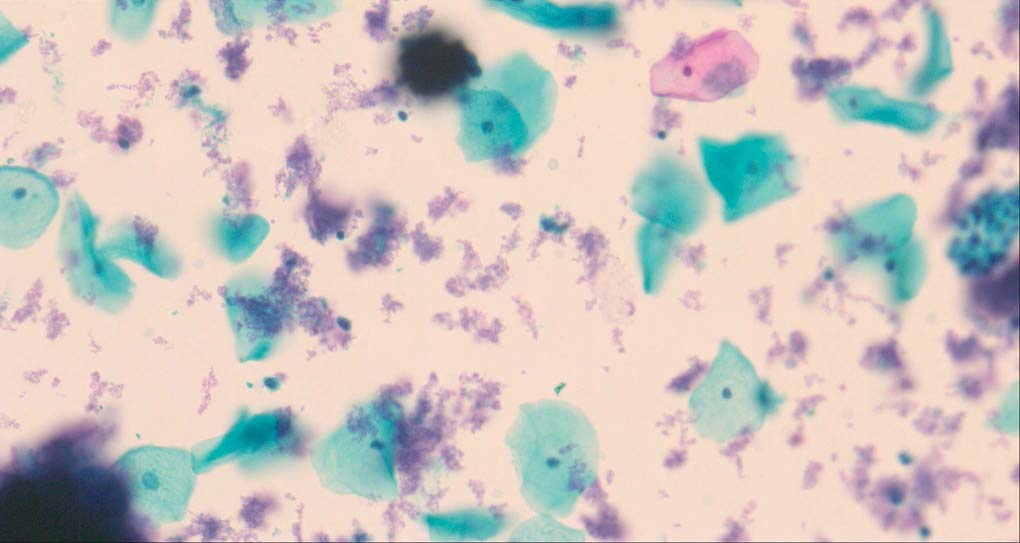

A good image fusion method should contain the following properties. First, it preserves both the details of small size objects and the integrity information of large size objects in the fused image, even in the case of the size of the interested objects varying largely in the image. For example, the cervical cell images from the microscope contain both small size isolated cells and large size agglomerates, which are both useful for cervical cytology [5]. Second, it should be efficient enough to handle large-scale data. For instance, it needs to process thousands of fields of view (FoV) in an acceptable time for the whole slide scanning in digital cytopathology [6], which requires to fuse a series of high resolution images captured at each FoV in a very efficient way. Third, it does not produce obvious artifacts. Despite being studied extensively, to our best knowledge, existing fusion methods may not meet these requirements simultaneously.

To demonstrate the effectiveness and efficiency of the proposed image fusion method , we conduct a set of comparative experiments on three image datasets. The first is composed by 8 pairs of multi-modal medical images and the second one contains 15 pairs of multi-focus gray or color natural images. These two datasets are often used in many related papers and some examples are shown in Figure 3(a) and Figure 3(b). The third one is a new multi-focus cervical cell image dataset collected by ourselves, which consists of 15 groups of color images and each group contains a series of multi-focus cervix cell images with size of or , etc. Some source examples are shown in Figure 3(c). Our source code implemented in C++ along with the new multi-focus cervical cell image dataset is available online.

Figure 9, Figure 10 and Figure 11 show the comparative fused results of the multi-focus cell images shown in Figure 3(c). For clarity, we also present a closeup view in the right-bottom of each sub-picture in Figure 9 and Figure 10. As shown in the close-up views of Figure 9, the fused images based on DSIFT, IM, MWGF and BF methods are extremely blurred in the boundary and fail to keep the details of cell nucleus. Furthermore, the DTCWT and NSCT based methods produce halo artifacts in the fused images, while GFF and CNN based methods fail to preserve the small cell nucleus. LP-SR based method nearly works fine which keeps the most of the details of the small size cells, but the integrity of the clustered large size cells is damaged. Fortunately, in our proposed method, the integrity of the clustered large size cells is preserved and most of the isolated small size cells are maintained from the original images, which demonstrates the best visual quality.

Similarly, as shown in the close-up views of Figure 10, the fused images from DSIFT, IM, MWGF and BF are blurred and lose some nucleus details, while the results from DTCWT, GFF, CNN and NSCT produce halo artifacts. LP-SR based method can keep details well but also produces halo artifacts and other noise. Our method can preserve the focused areas of different source images well without introducing any artifacts. For the example illustrated in Figure 11, the fused images generated by DSIFT, DTCWT, IM and NSCT all fail to preserve the focused areas of different source images and result in extremely blurred images. The GFF, CNN, MWGF and BF based method introduces a lot of color distortion of the nucleus regions and the obvious halo artifact. The result of LP-SR based method is close to the one of our method but introduces some odd color distortion. Again, our method produces fused image which can preserve the focused areas of different source images well without introducing any artifacts.